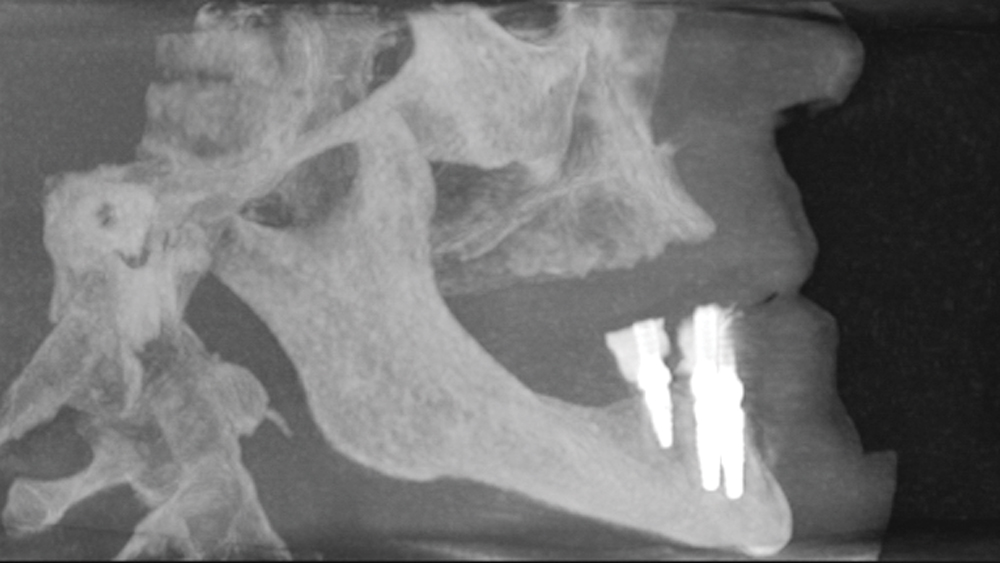

This patient was unhappy with the esthetics of her existing upper denture as well as the discomfort and instability caused by her loose-fitting mandibular partial denture. Although her concerns with the maxillary denture could be addressed with a new, more esthetic appliance, she preferred implant treatment for her mandible, where a fixed solution was needed to adequately restore function, stability and comfort.

Treatment plan:

The patient’s remaining mandibular teeth were extracted followed by immediate implant placement and delivery of a fixed provisional appliance. After integration of the implants, the prosthetic designs for the new upper denture and lower implant restoration were determined in tandem. Ultimately, the dual-arch restorations addressed the functional and esthetic challenges of the case while staying within the financial means of the patient, demonstrating the benefits of a flexible, multifaceted approach to restorative dentistry.